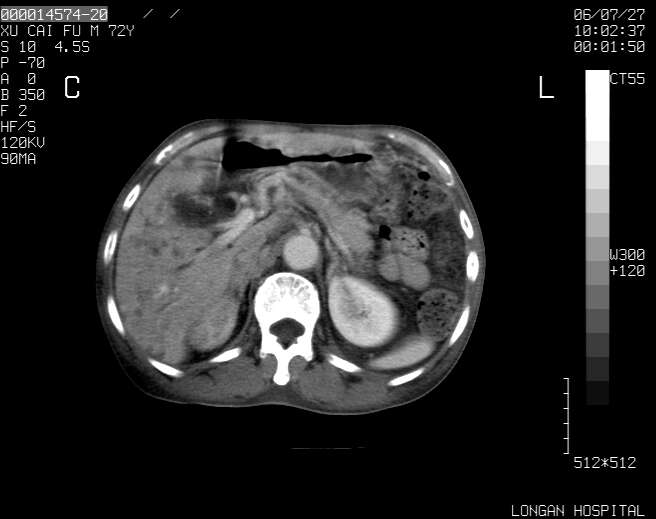

以下是引用winter在2006-7-30 20:14:00的发言:[br]1、考虑胆囊癌伴胆道侵犯并高位胆道梗阻、肝内多发转移、腹膜后淋巴结转移。[br]2、右肾轻度积水。[br]3、老人家72岁了胰腺头体尾部均较饱满,不过未见密度异常及其他异常征象。[br]4、腹水。

以下是引用jiajie在2006-7-31 7:10:00的发言:[br]考虑肝转移瘤,腹膜后淋巴结增大。[br]胃癌不能除外,建议胃镜检查。